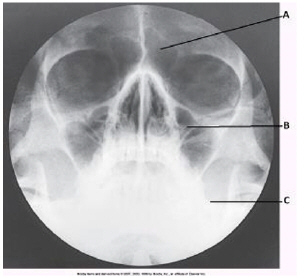

which paranasal sinuses are labeled with the letter A in this image

frontal

letter B

letter C

maxillary sinuses

letter D

sphenoid